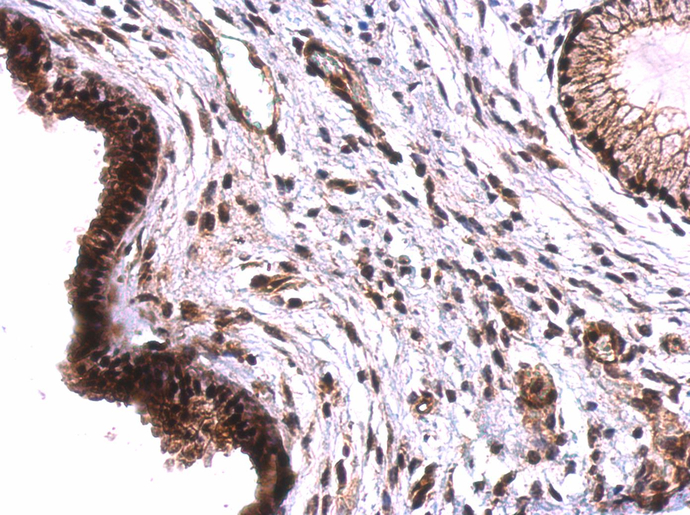

Anti-TET2 antibody [N2-2], N-term used in IHC (Paraffin sections) (IHC-P). GTX124205

GTX124205 IHC-P Image

TET2 antibody [N2-2], N-term detects TET2 protein on human cervical carcinoma by immunohistochemical analysis.

Sample: Paraffin-embedded cervical carcinoma.

TET2 antibody [N2-2], N-term (GTX124205) dilution: 1:500.

Antigen Retrieval: Trilogy™ (EDTA based, pH 8.0) buffer, 15min